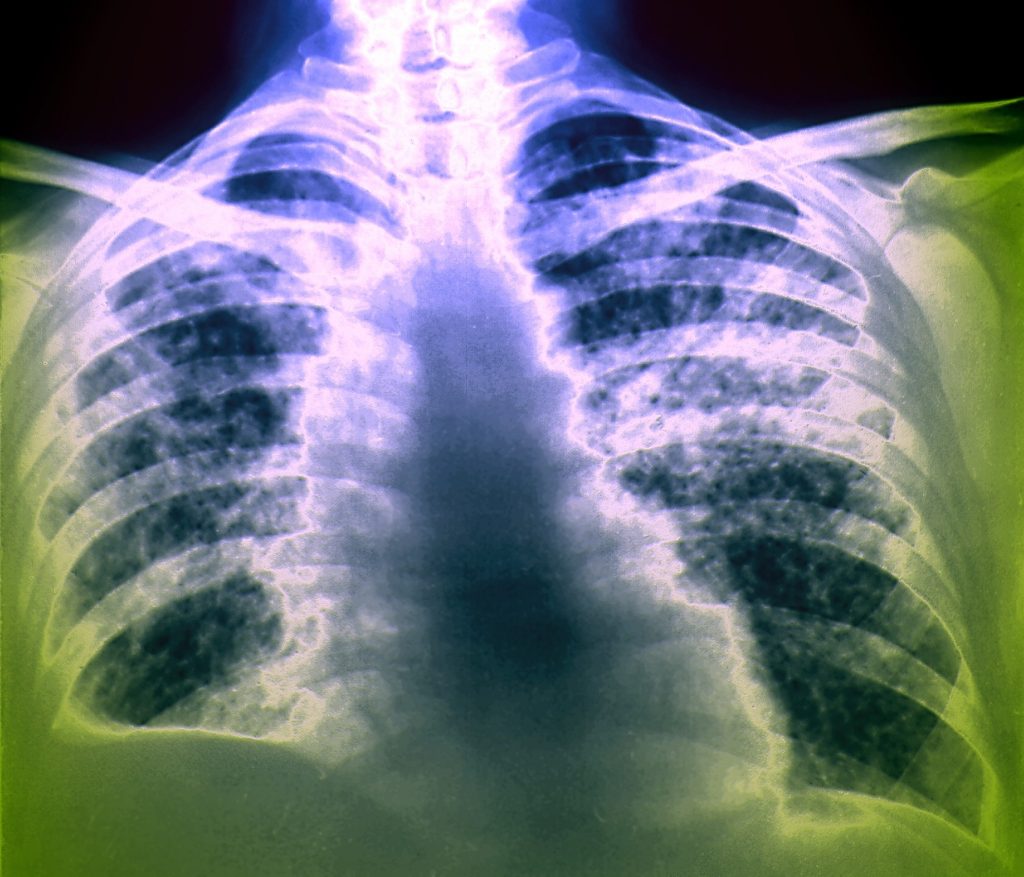

Pljučni rak je prva oblika raka po umrljivosti na svetu. Leta 2020 je zaradi bolezni umrlo 1,8 milijona ljudi. Nedrobnocelični rak pljuč je najpogostejša oblika pljučnega raka.